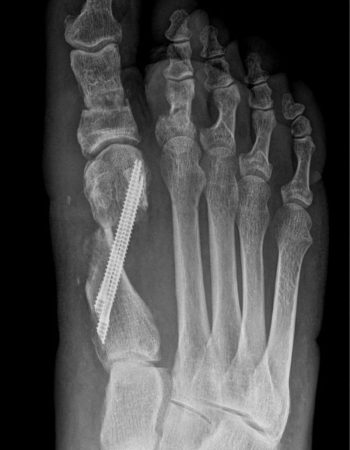

El caso que presentamos es muy representativo de la capacidad de corrección de la cirugía percutánea de tercera generación en la deformidad de Hallux Valgus. Se trata de una paciente con dolor a nivel del bunion y metatarsalgia con un 2º dedo sobre el primero que también le causa intolerancia con el calzado. Fue sometido a una técnica percutánea llamada MICA (Minimal Invasive Chevron Akin), sin ingreso y permitiendo carga inmediata

En las imágenes radiográficas se observa cómo se consigue una gran corrección en la posición de los dedos y una reducción de los sesamoideos sobre la cabeza metatarsiana. La fijación con tornillos nos va a permitir mantener esa reducción y estabilizar el montaje para reducir el dolor postoperatorio y permitir una buena consolidación ósea, como se ve en la última imagen.